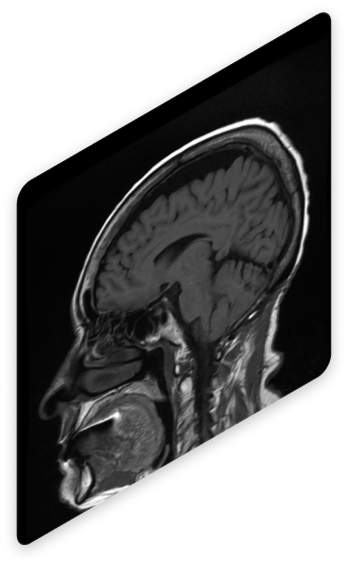

Visualización de las Adquisiciones

Revisa las imágenes adquiridas desde un visor profesional

El simulador incluye un visor integrado que permite interactuar con las imágenes, explorar cortes anatómicos y obtener una comprensión detallada de los resultados.